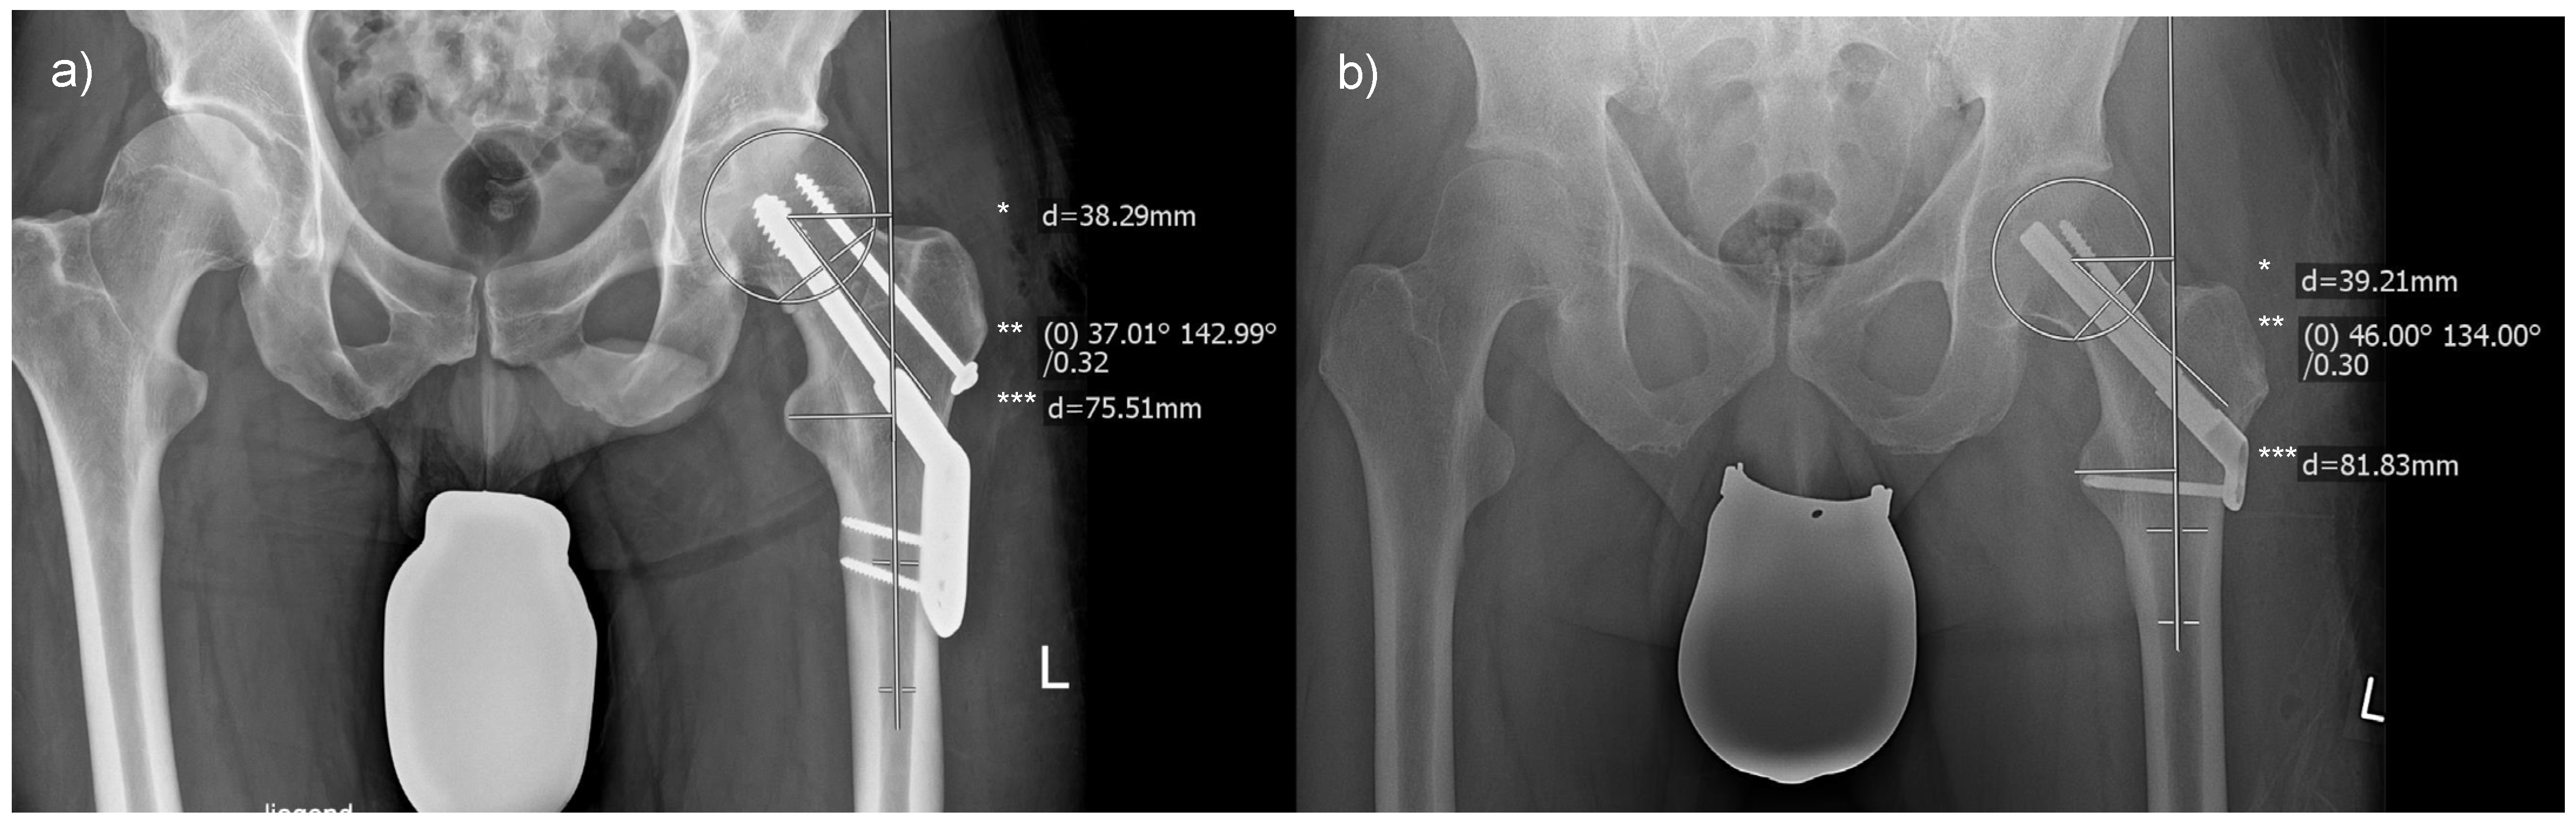

As depicted in Figure 1, radiographic assessments were conducted in a standardized fashion using MERLIN Diagnostic Workcenter. Figure 3 provides an illustrative representation of the respective measurements for femoral offset, the CCD angle, and the radiographic leg length associated with each incorporated implant. The outcomes of each evaluation were directly annotated by the software within the radiograph.

Figure 3.

Measurements of radiographic outcome measures: (a) displays the measurement of a femoral neck fracture treated with a DHS, and (b) with an FNS. Abbreviations: *, femoral offset; **, centrum–collum–diaphyseal angle; ***, leg length.